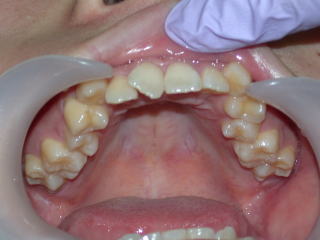

2022年7月25日初診、20代女性の叢生症例 (新潟県長岡市要町 要町歯科 歯科矯正 歯列矯正)

前歯のデコボコが気になる、とのことです。